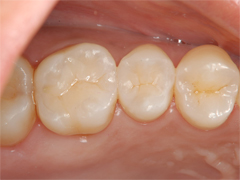

セラミックインレー装着

精密な治療を行うということは余計に歯を削りすぎることも防ぎます。

結果、神経を取らずにすんだり、痛みの少ない治療を行うことができるのです。